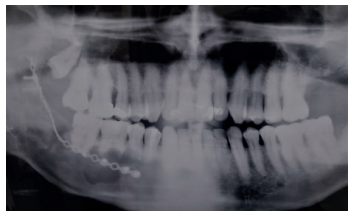

Dicha sensación de parestesia todavía perduraba en la última revisión realizada a los seis meses después de la intervención, momento en que se realizó una nueva radiografía panorámica. En ella se aprecia una buena osificación del gran defecto remanente (Figura 14).